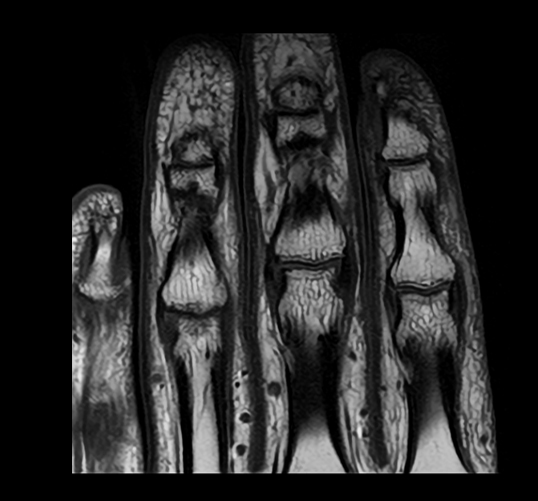

キヤノンのMRI装置で撮像した手の指の臨床画像